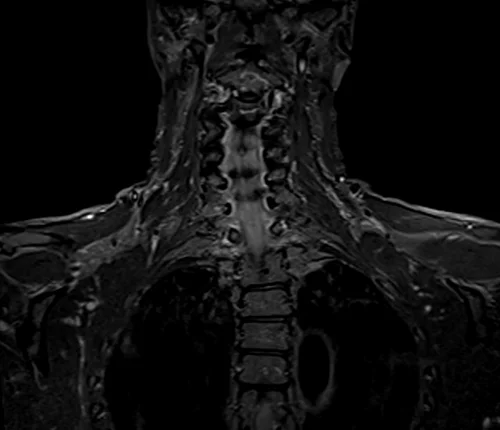

BRACHIAL PLEXUS